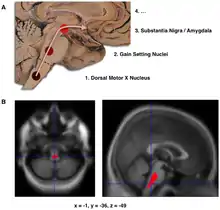

- التقدم الأولي التخطيطي لرواسب الجسم ليوي في المراحل الأولى من مرض باركنسون، على النحو الذي اقترحه براك وزملاؤه

- توطين منطقة خفض حجم الدماغ في مرض باركنسون مقارنة مع مجموعة من المشاركين دون المرض في دراسة التصوير العصبي، والتي خلصت إلى أن الضرر في الدماغ قد يكون في أول مرحلة يمكن تحديدها من الاعتلال العصبي لمرض باركنسون